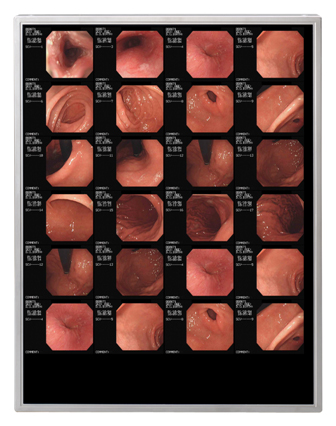

医療現場における液晶表示装置の普及に伴い、液晶表示装置に求められる性能はさらに高度化しています。特にここ数年は医療用画像処理技術が飛躍的に進展し、X線画像などのモノクロ画像と、3D-CT(注1)やFusion(注2)などのカラー画像の両方を読影診断できる高輝度タイプのカラー液晶ディスプレイの需要が高まっています。

このたびの新製品は、このSFT技術をさらに改善し、全モデルで1400:1の高コントラストを実現しています。特にカラーモデルはモノクロ画像もカラー画像もストレスなく読影診断することが可能で、近年の医療分野におけるカラー液晶ディスプレイへの要望に応えるものです。また、長寿命白色LEDバックライトを採用することで、医療用機器の分野でも要請が高まっている水銀フリー化や低消費電力化に貢献するとともに、24時間稼動などの厳しい使用環境が想定される医療機器でも、安定した表示性能を長く発揮します。さらに当QXGAモデルとUXGAモデルは同一の外形寸法を採用しており、お客様セットでのラインアップ展開が容易になります。